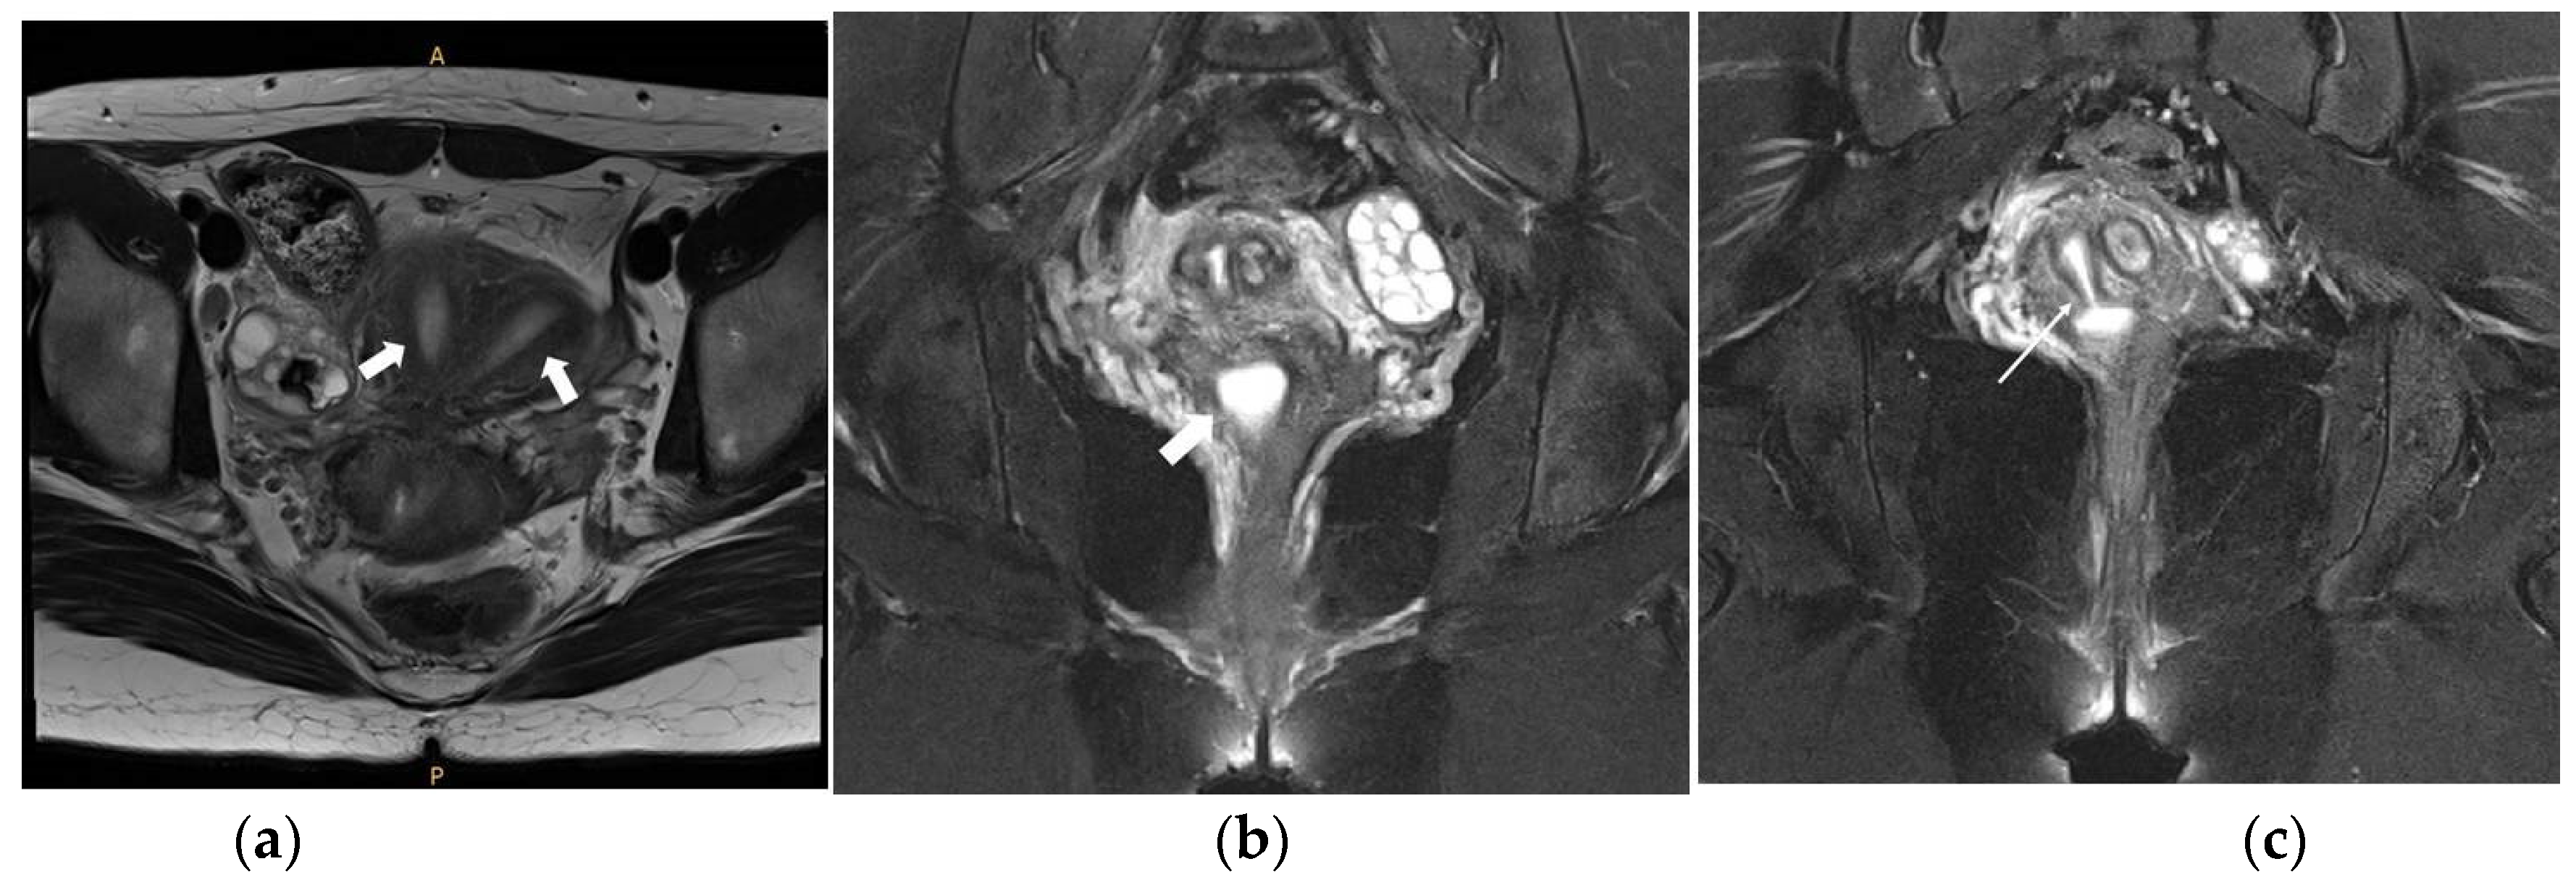

Figure 1. (a) Coronal view of abdominopelvic CT image suggesting Herlyn-Werner-Wunderlich syndrome. Uterine didelphys, hematocolpos of obstructed hemi-vagina, and ipsilateral renal agenesis are noted with white arrows.; (b) Coronal view of pelvic MRI T1-weighted image suggesting Herlyn-Werner-Wunderlich syndrome. Uterine didelphys and hematocolpos are noted with white arrows.

Figure 5. Pelvic MRI images. (a) Axial view T2-weighted image showing the two uterine corpuses (indicated with two white arrows); (b) Coronal view T2-weighted image showing the small cystic mass filled with fluid suggesting hematocolpos on the right side (indicated with a white arrow); (c) Coronal view T2-weighted image showing the hematocolpos connected with the right endometrial cavity (indicated with a white arrow).

On the abdominopelvic CT image taken at the ER, we noticed she had HWW syndrome (right side hemi-vagina and right kidney agenesis) with acute pyelonephritis (APN) of the left kkidne (Figure 3a,b). After admission, transvaginal USG (Figure 4) and pelvic MRI (Figure 5a–c) were performed. We planned to perform the vaginal wall resection surgery on the next menstrual period as she needed antibiotics treatment for the APN, and the amount of hematocolpos was not so extensive that we could not clearly identify the bulging vaginal wall.